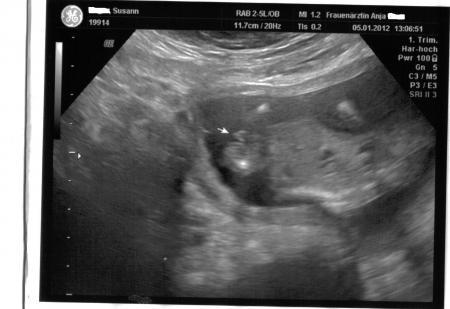

Hallo Ihr lieben, nach dem ich mit Termin heut 3 STUNDEN !!!warten musste habe ich noch erfahren das Sie keinen Ultraschall macht ok dachte ich mir dann Bezahle ich halt hauptsache ich seh mein Baby . Gesagt getan meinem Baby geht es super es hat Geschlafen aber sowas von Süss das glaub ihr garnicht. Er ist 9,5 cm "groß" und 104 gramm "schwer". Sie hat auch noch mal gesagt das er (warscheinlich) ein Junge wird. ich bin heute 15+0 ssw laut untersuchung 15+2 ssw. Ach Mädels ich freu mich so das mit meinem Baby alles ok ist aber ein wehmutstropfen gab es noch ich habe 1,6 kg zugenommen ich habe gefragt ob das ok ist und sie sagte ja beim 2 kind nimmt man schneller zu na toll das macht mut . so jetzt möchte ich euch nicht weiter stören. ich hänge euch noch die Bilder von heute an lg und einen schönen abend

Bild zu Bericht vom Frauenarzt + Fotos - Forum für Juli - Mamis

Erstmal muss ich sagen, dass dein Kleiner echt knuffig ist... schöne und recht eindeutige Bilderchen und wow er ist schon fast 10cm groß... ist das die Gesamtlänge oder SSL? Und mir ist aufgefallen, dass der kleine Mann ja jetzt schon schwer ist wie ne Tafel Schoki echt toll. Wieviel musstest du den für den US bezahlen?... aber gut, dass du es gemacht hast, nun biste beruhigt und weißt sogar was es wird... hätt ich auch gemacht... LG deine Keksi

schön, dassdein baby so toll gewachsen ist. es sieht wirklich nach einem jungen aus. schöne fotos.